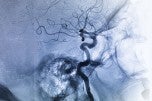

Image